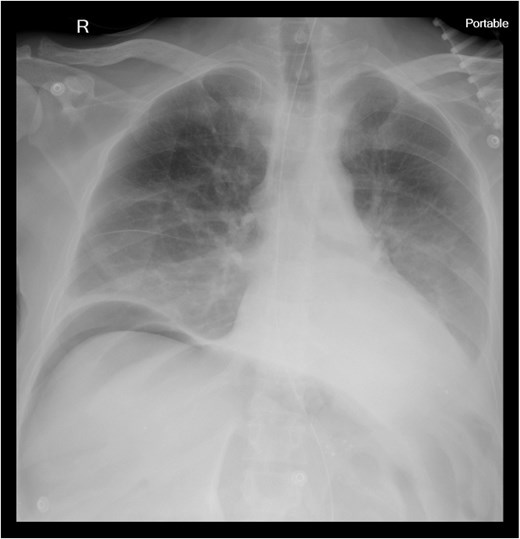

Chest X-ray revealed pneumoperitoneum (Fig. 1), and computed tomography (CT) scan confirmed free intraperitoneal air with no evident abscess (Fig. 2). The patient was admitted to the intensive care unit, resuscitated, and underwent urgent exploratory laparotomy.

CT scan of abdomen and pelvis: pneumoperitoneum and polycystic disease in the kidneys, liver, and pancreases.